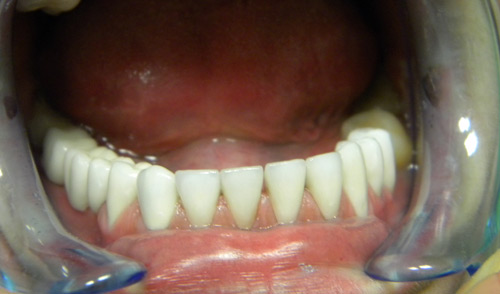

• Metalokeramičke krunice (poslije)

• Bezmetalna keramika (poslije)